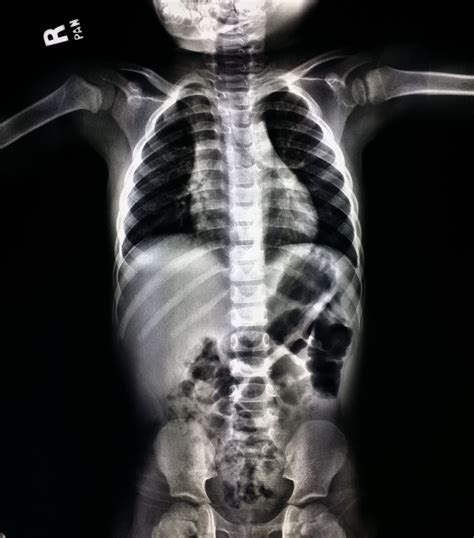

A Baby X-ray is a diagnostic imaging test that uses a small amount of radiation to create images of the bones, organs, and tissues within the body. Infants are not miniature adults; their bodies are constantly growing and changing, which is why pediatric imaging requires specialized care. Doctors typically request an X-ray for several common reasons:

- Respiratory Issues: If a baby is struggling to breathe, wheezing, or has a persistent cough, an X-ray can help identify conditions like pneumonia, bronchiolitis, or other lung infections.

- baby x ray pictures